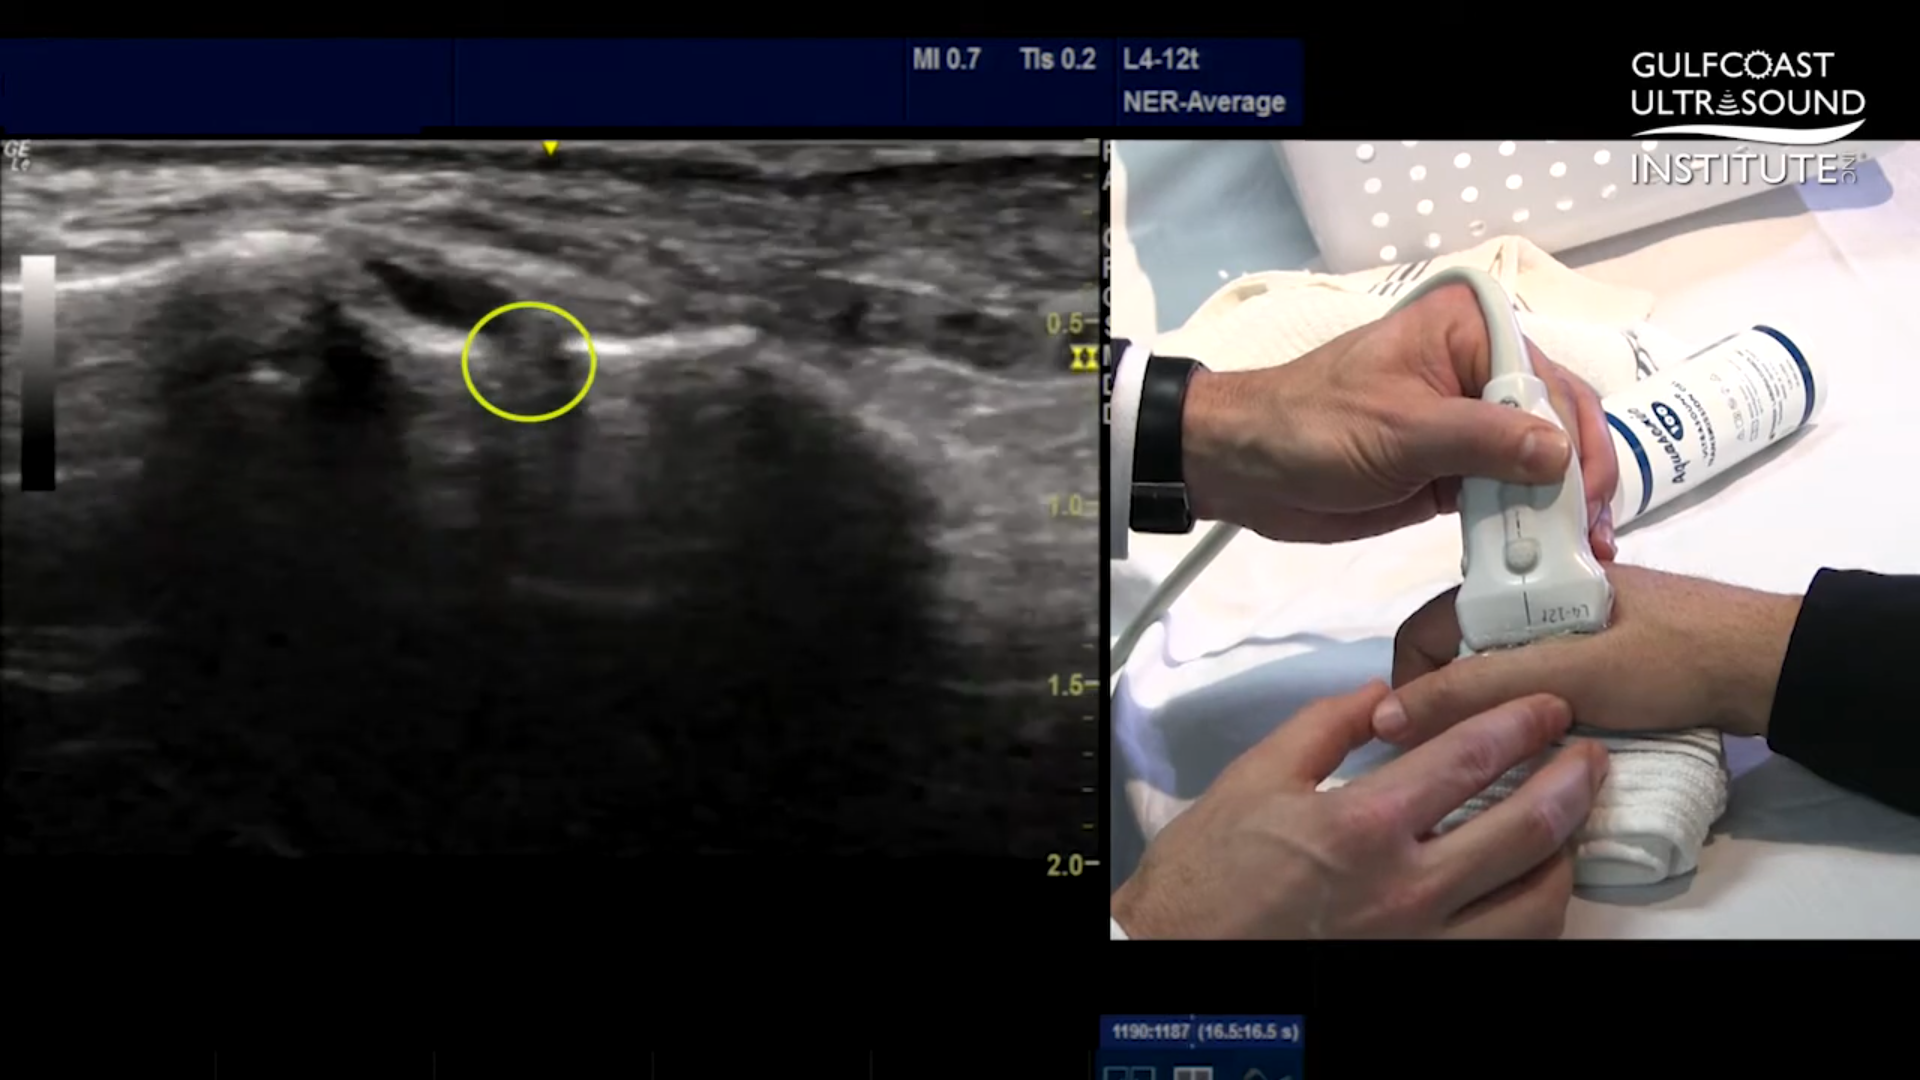

Key Visual Landmarks to Look For

During the scan, clinicians focus on specific bone contours and the position of the adductor aponeurosis. These landmarks are essential for distinguishing between a standard ulnar collateral ligament tear and a more complex Stenner lesion. A Stenner lesion occurs when the torn ligament becomes displaced and trapped, preventing natural healing. Ultrasound makes it possible to recognize this condition by observing how the ligament and surrounding tissues move or fail to move during the exam.

Using Dynamic Stress Techniques to Reveal Hidden Injuries

One of the most valuable aspects of ultrasound evaluation is the ability to perform dynamic testing. The tutorial highlights a stress technique that involves applying gentle pressure to the thumb joint while scanning. This maneuver can reveal fluid accumulation or joint widening that might not be visible at rest. In cases of partial or hidden ruptures, these subtle changes are often the key to an accurate diagnosis.